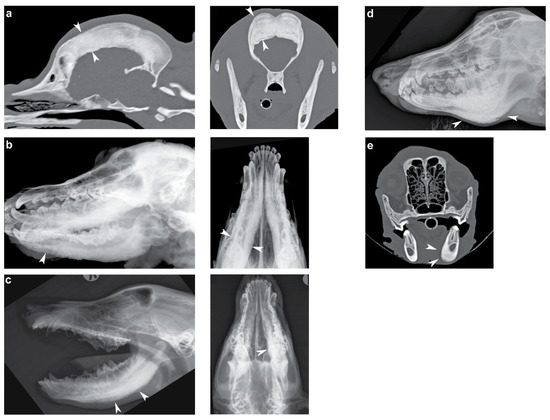

3.1. Phenotype